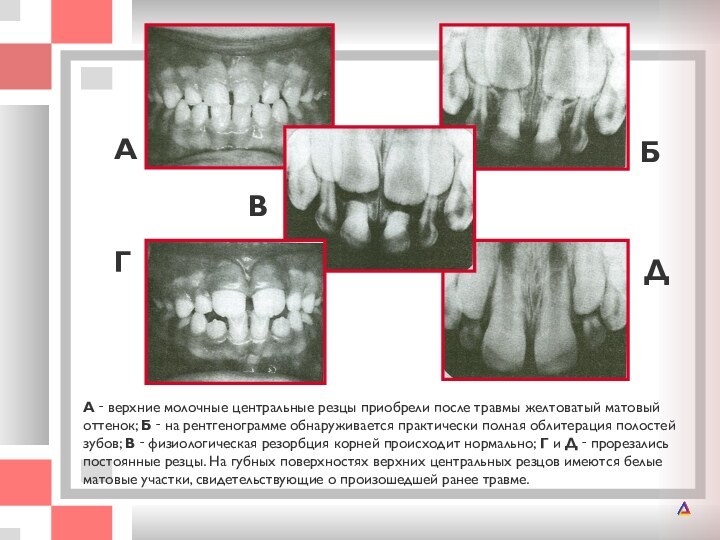

А ‑ верхние молочные центральные резцы приобрели после травмы желтоватый матовый

травмы желтоватый матовый оттенок; Б ‑ на рентгенограмме обнаруживается

практически полная облитерация полостей зубов; В ‑ физиологическая резорбция корней происходит нормально; Г и Д ‑ прорезались постоянные резцы. На губных поверхностях верхних центральных резцов имеются белые матовые участки, свидетельствующие о произошедшей ранее травме.